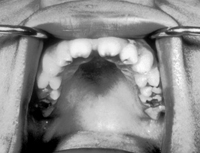

Tuy hầu hết các u lành tính không gây nguy hiểm đến tính mạng bệnh nhân, nhưng một số ít khối u sẽ tái phát sau khi đã được cắt bỏ rồi, như trường hợp u men răng và u hỗn hợp tuyến mang tai (tumor mix) có khi cũng biến thành u ác tính.